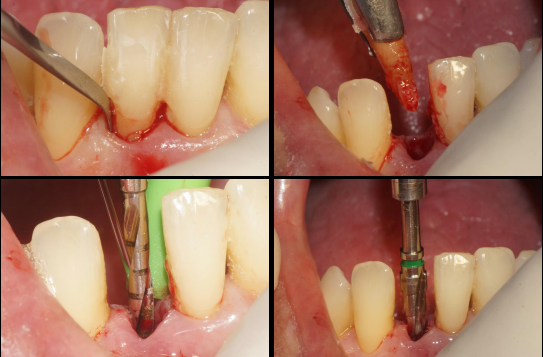

Após 35 dias da instalação do implante foi realizada a abertura do implante através de um bisturi circular e o pilar Ideale reto de 3.3 X 4.0 X 2.5 mm foi torqueado no implante a 20 Ncm. Foi realizada também uma moldagem deste pilar com o seu transferente correspondente e a prótese adesiva voltou a ser instalada. Depois de uma semana, o provisório parafusado confeccionado no laboratório foi instalado e mantido em posição durante 15 dias para formar um novo perfil de emergência, aproximando as características dos tecidos circundantes às características de um incisivo central inferior. Neste momento, foi realizada uma nova moldagem da região e uma coroa metalocerâmica foi confeccionada e instalada após uma semana. Foi também realizada a radiografia.